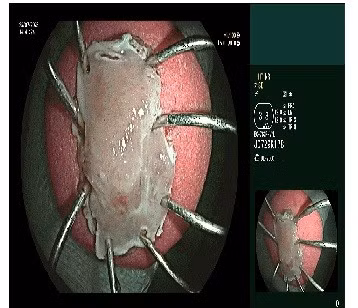

Can thiệp nội soi cắt tách niêm mạc ống tiêu hóa ESD để loại bỏ tổn thương thực quản - Ảnh BVCC

Trước ca lâm sàng phức tạp, kíp bác sĩ khoa Thăm dò chức năng đã tiến hành can thiệp nội soi cắt tách niêm mạc ống tiêu hóa ESD để loại bỏ tổn thương thực quản.

Kết quả giải phẫu bệnh xác định đây là ung thư biểu mô vảy tại chỗ, giai đoạn sớm của ung thư thực quản.

Đây là kỹ thuật tiên tiến, ít xâm lấn, cho phép lấy trọn tổn thương ung thư giai đoạn sớm mà không cần phẫu thuật. Sau khi kiểm soát khối u thực quản, bệnh nhân được tiếp tục chỉ định phẫu thuật nội soi cắt đoạn trực tràng chứa khối u sigma kèm nạo vét hạch.